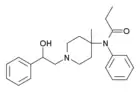

- Part IV

The modifications covered in this diagram have to do with stereochemistry and the assignment of unique Cahn-Ingold-Prelog R/S assignments to complex analogues of fentanyl. The stereochemistry of fentanyl analgoues can seem at first counter-intuitive, because of the complex and unique nature of the reasoning organic chemists must develop to internalize complex three dimensional geometries such as those needed to comprehend stereochemistry. Thankfully these images follow a simple procedure for organizing a potential analogue of fentanyl into the total number of unique stereoisomers, the number of true stereocenters on the molecule, and the number of Cahn-Ingold-Prelog R/S assignments that are appropriate for that analogue.

The procedure used in the analysis of stereochemistry in these series of images is the following:

- First the image is drawn out.

- Second asterisks are placed by potential stereocenters as indicators (*).

- Third the pairs of each stereocenters R and S orientations are combined through all possible permutations of stereocenters.

- Fourth the permutations are checked for super-imposability, indicating that they are varying around what is not a true stereocenter and therefore the permutations are truly the self-same stereoisomer.

This procedure will be used when making an assessment of the number of valid stereoisomers that an analogue of fentanyl will be predicted to have. Because the analogues of fentanyl are so large, and the moieities (sub-regions) of the molecule that are relevant to its chirality are so small, that we often reproduce the fentanyl analogue as a smaller, simpler molecule with the same number of, and dynamics between its, stereocenters. This saves significant space allowing us not to reproduce redundant material that consumes a lot of space on the image.

The first case studied here is fentanyl itself, or propionyl-4-anilino-N-phenethylpiperidine, the most well known of the fentanyl analogues and the eponymous molecule (namesake) for the whole chemical categorey. The only identified stereocenter is found at the 4-carbon, opposite the piperidine nitrogen but adjacent to the aniline nitrogen. This seems to be a stereocenter because of the apparent 4 unique substituents. We transfer this stereocenter to the equivalent molecule cyclohexanol, with an analogous apparent stereocenter. Once we draw out the potential stereoisomers, we see that the two structures are super-imposable in three dimensions, and therefore are the self-same molecule. For this reason fentanyl does not have R/S assignments.

The second case studied here is of 3-methylfentanyl. There are two potential stereocenters, at the 4-carbon and also at the 3-carbon, where there is additionally a methyl group. Now, we mark both 3 and 4 carbon as potential stereocenters with an asterisk (*), and see how many potential stereoisomers we can eliminate. We see that of the four permutations of stereoisomers, none are super-imposable in three dimensions, meaning each is a unique stereoisomer and that both potential stereocenters were true. This gives 4 potential R/S assignments, 1R3S, 1R3R, 1S3S, 1S3R. What is particularly interesting and quite a contrast from the previous example of cyclohexanol, is the stereocenter at C-4 is indeed a true stereocenter here, whereas in the pervious example of cyclohexanol as an analogy to fentanyl, the C-4 was not a true stereocenter. This changed because the modification of the C-3 carbon without an equivalent change on the C-2 carbon created an imbalance between two formerly identical substituents, creating a novel stereocenter where there was not one previously. This is why it is so important to follow the 4 steps in the above procedure every time, as "inherited procedural wisdom" may hold an organic chemist back in finding the true or correct answer.

- Part V

The third case studied here is alpha-methylfentanyl. This group contains a substitution similar to the 3-methylfentanyl that was examined in the previous example on the previous image in this series (Fentanyl Synthesis p4.png), but it is on the phenethyl chain as opposed to being implanted on the piperidine ring. We then mark the two stereocenters, one on the C-4 carbon just as on fentanyl itself, and the other on the C-α (alpha carbon). To analogize these stereocenters we chose N-(1-hydroxyethyl)-4-hydroxypiperidine. When we draw out all potential stereoisomers, we see that the C-4 stereocenter is super-imposable, eliminating it as a true stereocenter. This leaves only 2 R/S assignments that follow the orientation of the stereocenter at the C-α (alpha carbon) position for the real α-methylfentanyl. These are labeled 7S and 7R, a reflection of the stereocenter in the piperidine derivative we used being at C-7 position. It is interesting that the C-4 stereocenter, which has no chiral activity in fentanyl (1st example), activiates it in 3-methylfentanyl with an on-the-ring addition, and loses it again in α-methylfentanyl with an off-the-ring addition.

The fourth case studied here is ohmfentanyl. Ohmfentanyl has 3 potential stereocenters, which are best analogized by another piperidine derivative: N-(1-hydroxyethyl)-3-methyl-4-hydroxypiperidine. This uses a similar structure to analogize the three potential stereocenters in ohmfentanyl, namely the 4-C, the 3-C, and the β-C (beta carbon). These three stereocenters are analogized in the C-4, C-3, and C-7 respectively. When we draw all potential stereoisomers out we see that they are not super-imposable in any combination of pairing, and therefore we have 8 unique stereoisomers and 3 true stereocenters. This yields 8 unique R/S assignment combinations which are outlined as captions under the stereoisomers of the analogous molecule.

These fundamentals are typically enough to help a chemists navigate the world of fentanyl analogues proficiently. Other substituents and substitutions generally follow the naming conventions outlined in this section. However, the presence of three six-membered rings which can each be independently substituted can easily lead to confusion, especially with the inconsistent use of prime notation.

For instance, 4-methylfentanyl, 4'-methylfentanyl and 4"-methylfentanyl are all known compounds, as are 3-methylthio-fentanyl and 3-methyl-thiofentanyl, all of which have varying potencies and pharmacokinetics.

Confusion between different positional isomers is especially significant in the case of fentanyls because of the huge variation in potency between different members of the class.[47] The weakest compounds such as benzylfentanyl are around the same potency as codeine (i.e. approximately 1/10th the potency of morphine), while the strongest compounds such as carfentanil and ohmefentanil can be over 10,000x more potent than morphine, meaning there is a 100,000-fold variation in potency between the strongest and weakest fentanyl derivatives. This means that two positional isomers with the same molecular weight, which may be difficult to tell apart without detailed chemical analysis, may be hundreds or even thousands of times different in pharmacological potency. Also the wide variety of substitutions that have been used on the basic fentanyl structure, each of which can either reduce or increase the potency, can be unpredictable when used in combination, so it may be impossible to estimate the likely potency of newly discovered analogues until pharmacological testing has been carried out.